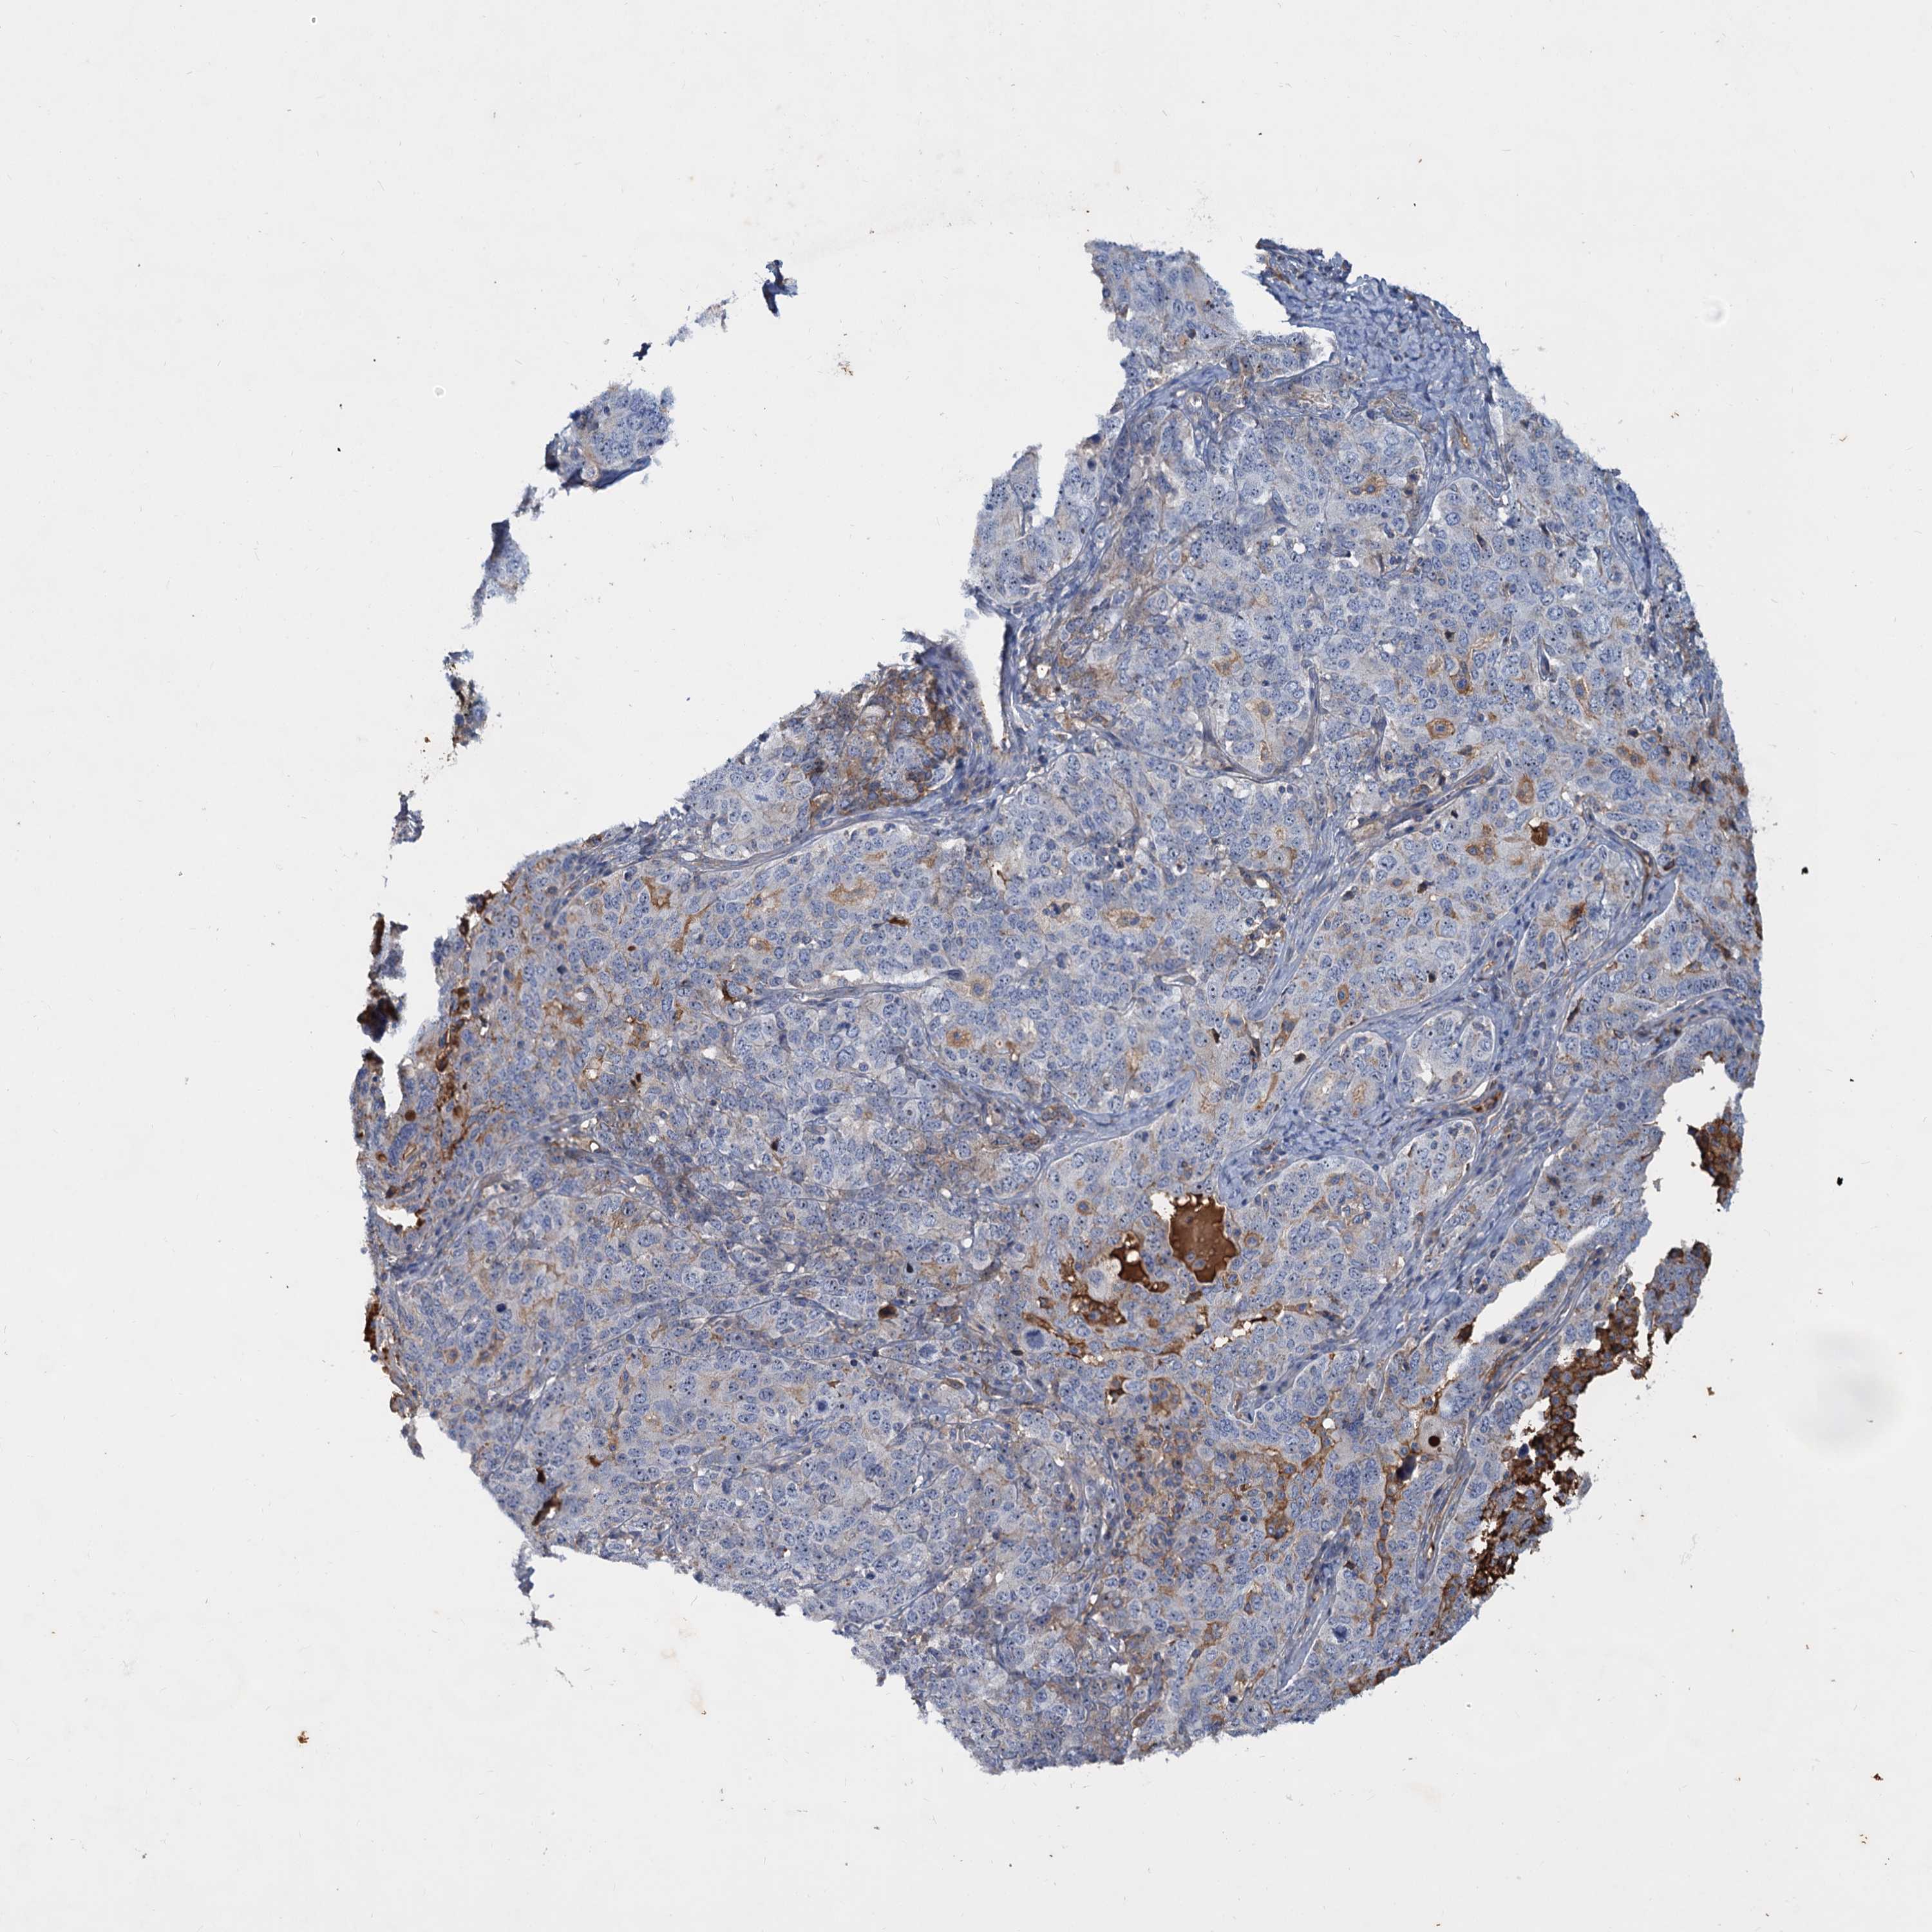

OVARIAN CANCER - Protein expressioni

A mouse-over function shows sample information and annotation data. Click on an image to view it in a full screen mode. Samples can be filtered based on level of antibody staining by selecting one or several of the following categories: high, medium, low and not detected. The assay and annotation is described here.

Note that samples used for immunohistochemistry by the Human Protein Atlas do not correspond to samples in the TCGA dataset.

Antibody stainingi

Antibody staining in the annotated cell types in the current human tissue is reported as not detected, low, medium, or high, based on conventional immunohistochemistry profiling in selected tissues. This score is based on the combination of the staining intensity and fraction of stained cells.

Each image is clickable and will lead to virtual microscopy that enables deeper exploration of all samples and also displays staining intensity scores, fraction scores and subcellular localization as well as patient and tissue information for each sample.

Antibody HPA035827

Staining

High

Medium

Low

Not detected

Intensity

Strong

Moderate

Weak

Negative

Quantity

>75%

75%-25%

<25%

None

Location

Nuclear

Cytoplasmic/membranous

Cytoplasmic/membranous,nuclear

Cystadenocarcinoma, serous, NOS

Carcinoma, endometroid

Cystadenocarcinoma, mucinous, NOS

Carcinoma, NOS